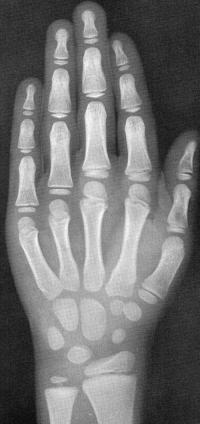

Sexo Masculino

8 anos

Fonte: GREULICH, W.W. & PYLE, S.I.: Radiografic Atlas of Development of the Hand and Wrist. Stanford University Press, 2° edition, 1959.